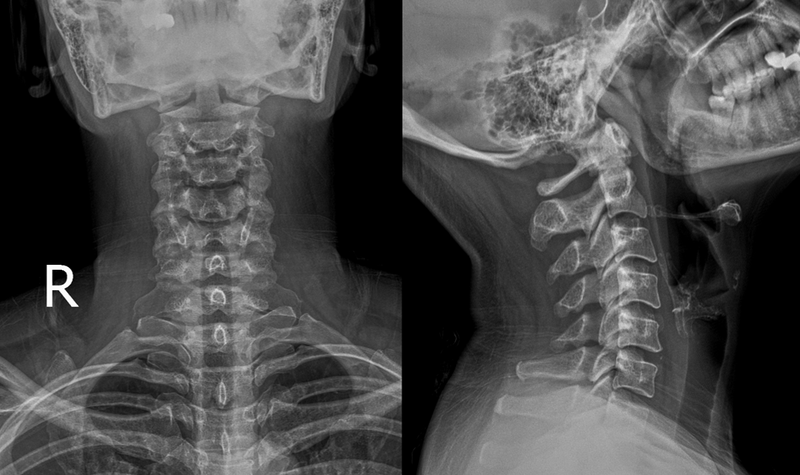

Chụp X-quang: Là phương pháp sử dụng tia X để mô phỏng chính xác cấu trúc xương. Khi tia X xuyên qua cơ thể, chúng bị hấp thụ ở mức độ khác nhau bởi các loại mô khác nhau, tạo nên hình ảnh cho thấy sự khác biệt về mật độ của các mô này. Phát hiện gãy xương, viêm phổi, nhiễm trùng, và nhiều tình trạng bệnh lý khác. Chụp X-quang cũng được sử dụng trong nha khoa để kiểm tra răng và xương hàm. Phương pháp này cung cấp hình ảnh nhanh chóng với chi phí thấp và thường chỉ cần một liều lượng tia xạ thấp, giúp chẩn đoán nhiều bệnh lý mà không gây ra tác dụng phụ nghiêm trọng.